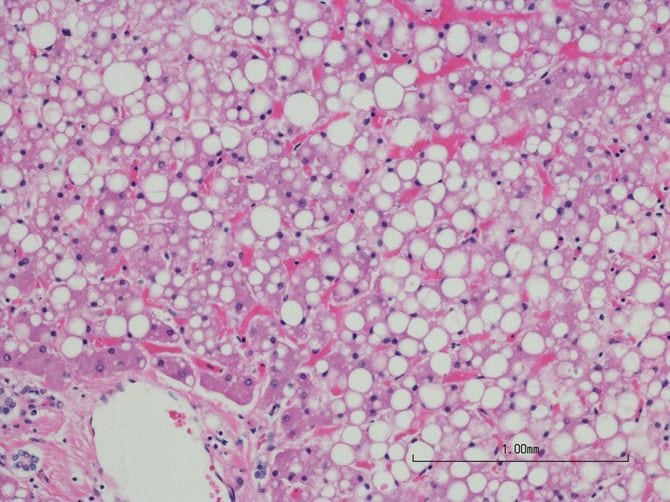

では、肝臓のどこに脂肪がたまっているのでしょうか。脂肪肝とは、肝臓を形成している細胞、つまり肝細胞の一つひとつの中に、水滴のような形で脂肪がたまっている状態なのです。

同じように脂肪肝の脂肪も、粘性はありますが、柔らかいものです。肝細胞の中に、ぷよんぷよんとした水滴のような状態で存在しています。